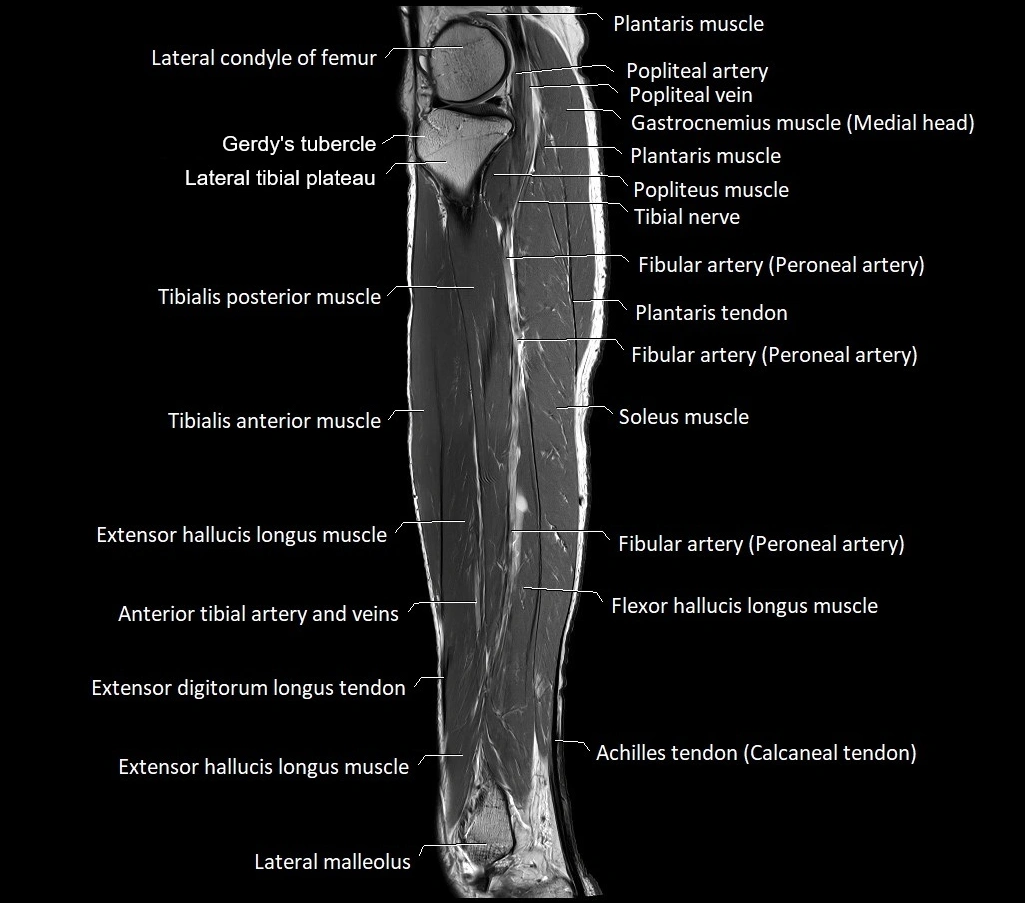

MRI image